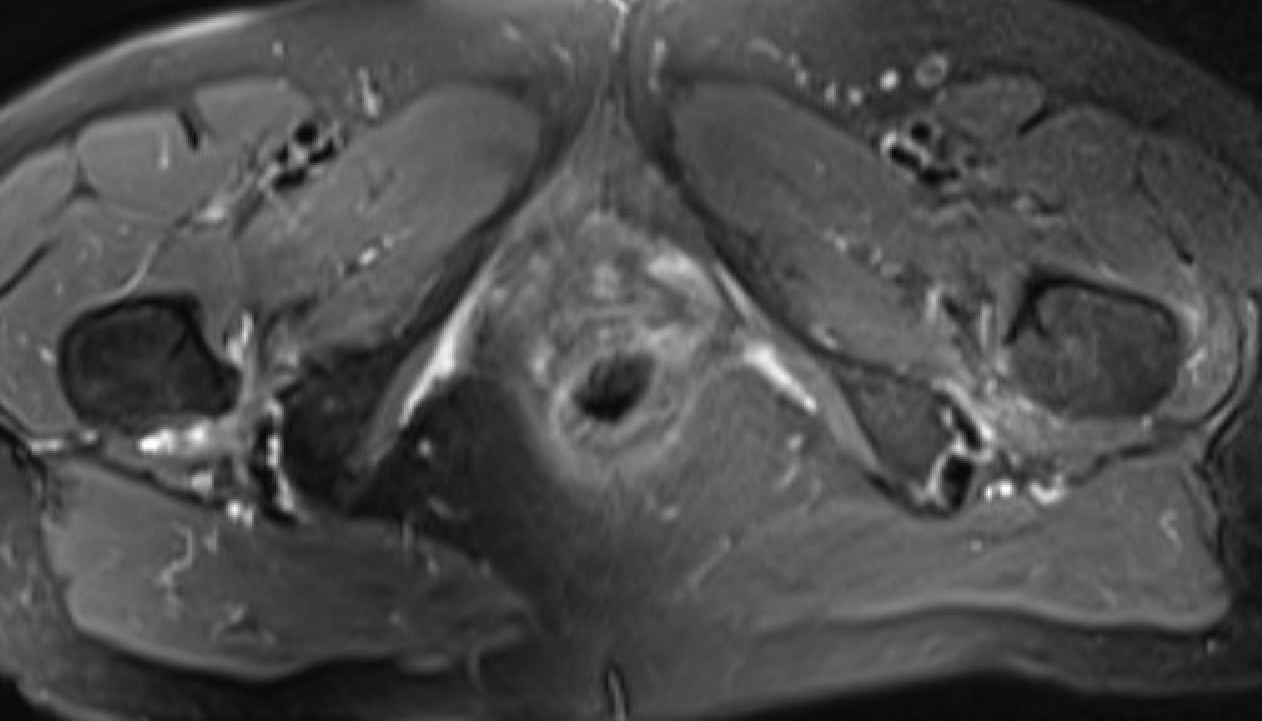

MRI

Reduced ischiofemoral space - distance between the lesser trochanter and the ischial tuberosity

Reduced quadratus femoris space - distance between hamstring tendon and iliopsoas

Inflammation / edema in quadratus femoris +/- fatty degeneration

IFIIFI

IFIIFIIFI

Singer et al Skeletal Radiol 2015

- systematic review of 190 hip MRI of patients with ischiofemoral impingement

- compared to controls

- ischiofemoral space < 15 mm: sensitivity  77%, specificity 81%, accuracy 78%

- ischiofemoral space < 10 mm: sensitivity 79%, specificity 74%, accuracy 77%.